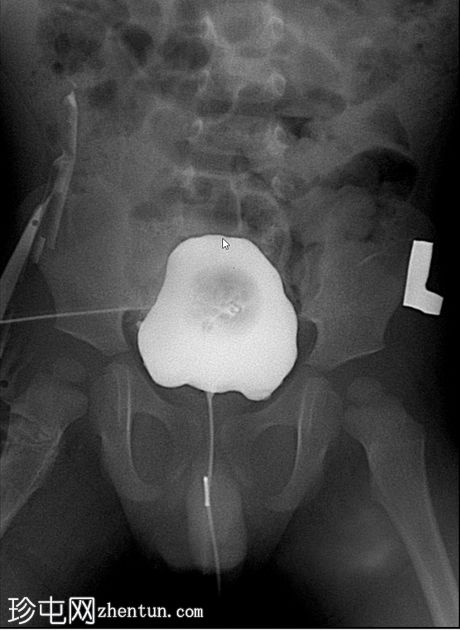

排尿影像

使用纱布进行外部压迫成功阻塞了脐尿管开口,膀胱充盈良好。左侧输尿管和肾盂肾盏系统可见膀胱输尿管反流,符合II/III级VUR。输尿管轮廓正常,无憩室,无管壁增厚。尿道显影正常,未见后尿道瓣膜或狭窄。无肾积水。

首次尝试使用Foley球囊阻塞脐尿管开口效果不佳。纱布阻塞法可提供更完整的密封,使造影剂得以充分滞留并充盈膀胱。这使得排尿期能够显示II/III级膀胱输尿管反流。